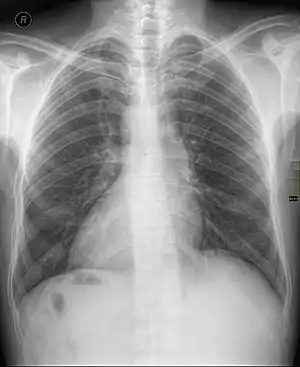

| Chest X ray of a person with dextrocardia situs inversus showing the cardiac apex pointing towards right | |